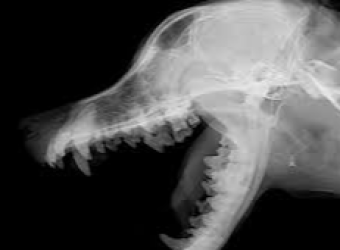

X-quang răng chó mèo tại Sing Pet Biên Hòa, Đồng Nai. Chẩn đoán sâu răng, viêm nướu, áp xe, răng mọc lệch. Hỗ trợ điều trị nha khoa và theo dõi hậu kiểm hiệu quả.